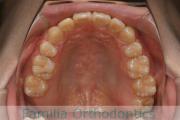

上顎

下顎

前歯の関係など

右側

正面

左側